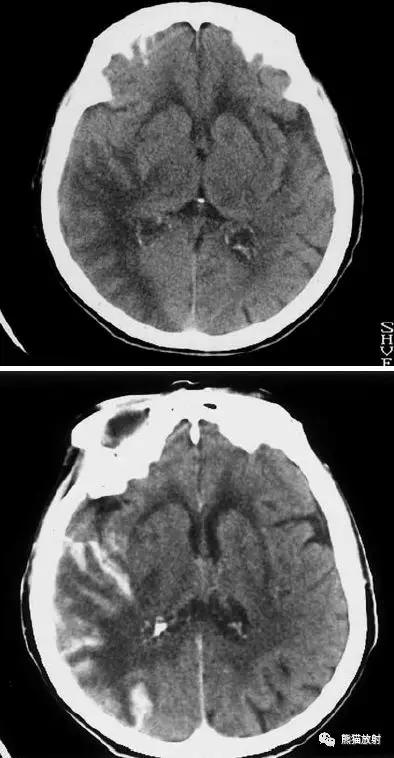

右侧大脑前动脉供血区部分梗死

右侧大脑后动脉供血区梗死

双侧大脑后动脉供血区梗死

右侧大脑前、中动脉供血区梗死,可见明显占位效应。